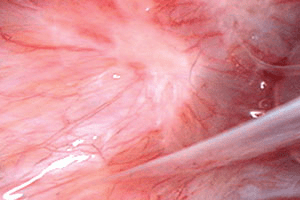

Il arrive qu’une patiente ait une endométriose visible dans le cul de sac vaginal postérieur (figure 2) qui est en fait la protrusion d’un nodule situé sur un ligament utéro-sacré ou sur le rectum. Il sera visible au cours de l’examen si le spéculum est orienté vers l’arrière. L’endométriose située sur une cicatrice de césarienne ou sur un ligament rond à sa sortie du canal inguinal se manifeste par des grosseurs douloureuses qui peuvent augmenter de taille pendant les règles.

Figure 2. L’endométriose du cul de sac vaginal postérieur a provoqué un amas épithélial (voir l’intérieur du cercle). Une endométriose vaginale peut être associée à une obstruction du cul de sac de Douglas et résulter d’une extension invasive de la maladie qui va des ligaments utéro-sacrés ou d’un nodule rectal vers le vagin.